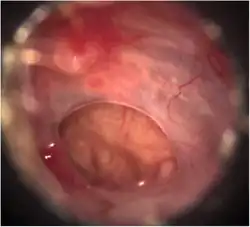

Existem diversas doenças que provocam uma perda da coloração normal da membrana timpânica, como as otites agudas, situação em que o tímpano adquire uma coloração mais ou menos avermelhada sobre um fundo seroso e purulento.[carece de fontes]

O médico diagnostica a perfuração examinando o ouvido com um aparelho especial, chamado de otoscópio. Se possível, testes de audição formais são realizados antes e após o tratamento.